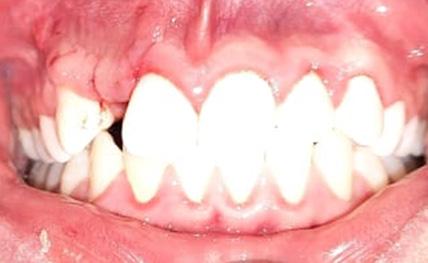

Durante el estudio, la cabeza de cada estudiante fue posicionada en relación al plano de Frankfurt (paralelo al piso), mismo que se logró con una regla nivel de 30 cm; dicho plano anatómico se extiende desde el agujero infraorbitario a la parte media del borde superior del conducto auditivo externo (12), estos reparos anatómicos se identificaron en el estudiante mediante la palpación digital del borde inferior de la órbita y a simple vista del trago del pabellón auricular (figura 1).

Quelca-Portugal-Yujra-Chuquimia

Seguidamente y mediante palpación se localizó de forma bilateral el ángulo mandibular, el reborde orbitario lateral y la arteria facial de cada estudiante, ésta última estructura se identificó a nivel del borde inferior del maxilar inferior, percibiendo sus pulsaciones con facilidad. Con un lápiz dermográfico se marcó un punto en la piel donde se localizó a estas tres estructuras. Desde el punto marcado que representaba a la arteria facial, se trazó una línea vertical y ascendente hasta la referencia anatómica más relevante, identificable y no modificable por procesos infecciosos submandibulares (arco cigomático). Finalmente se determinó la distancia entre el borde lateral de la órbita y la proyección vertical ascendente de la arteria facial sobre el arco cigomático (figura 1).

Fuente: Elaboración propia, julio 2019

Figura 1. Puntos y líneas utilizadas para la localización de referencia anatómica no modificable sobre la base de la arteria facial. Localización de referencia anatómica inmodificable sobre la base de la arteria facial en infecciones submandibulares odontogénicas